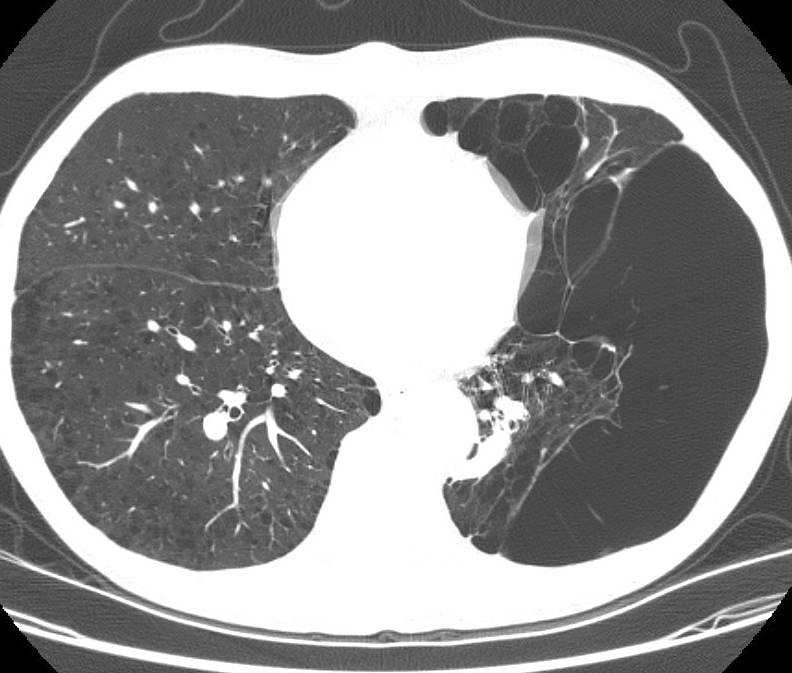

Gallery COPD bulla LLL CT2

bulla LLL CT2